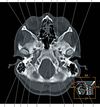

What are the important structures in the temporal bone you need to know about?

Show the location of the temporal bone and name the 3 main parts of the bone.